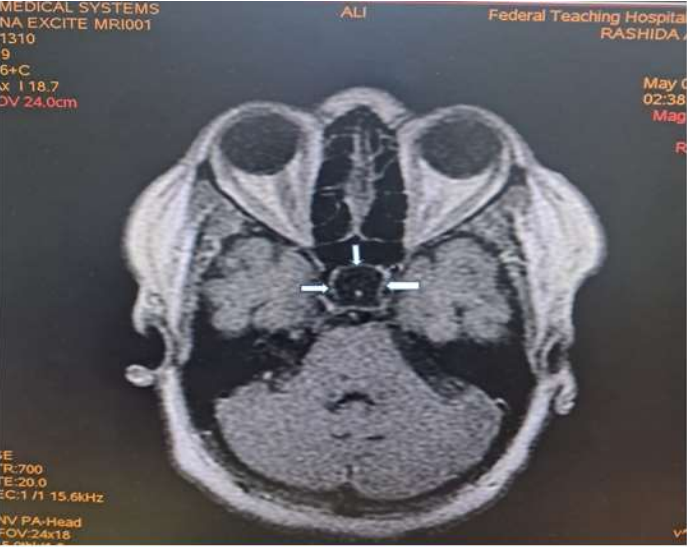

Magnetic Resonance Imaging (MRI) revealed expansion of the sella with a well-defined fairly rounded lesion measuring 15 X 14 X 15mm (width X AP X H). It is hypointense on T1W, hyperintense on T2W and suppressed on FLAIR sequence. Rim enhancement is seen post contrast. The mass is inseparable from the optic chiasma suggestive of compression.

Radiological diagnosis of Rathke cleft cyst was made with a differential of Cystic pituitary macroadenoma.

Figure 3: Axial T1W post contrast image of the brain showing a marginal (rim) enhancement of the hypointense rounded intrasellar mass lesion (white arrows).

Rathke’s cyst is visualised on magnetic resonance imaging as a lesion located in the intermediate lobe of the pituitary. Its largest diameter usually does not exceed 20 mm9. The cyst may have varying intensity against the cerebrospinal fluid, although it is more often hypointense in T1-weighted images and hyperintense in T2-weighted images. RCC image captured on MRI is described as “an egg in a shell [9]. The enhancement of the cyst wall following contrast administration suggests inflammation or metaplasia [11].

Due to its high soft tissue resolution, Magnetic Resonance Imaging (MRI) is the primary diagnostic technique for RCC9. It also determines the cystic content and fluidity of the cyst which is useful in planning for subsequent patient’s management10. Fifty percent are hyperintense on T1W (due to high protein content) while 50% are hypointense. On T2W, 70% are hyperintense, 30% iso or hypointense and 20% have hypointense rim. T1W Post contrast images usually show no enhancement. However, a thin enhancing rim may be seen when cyst wall infection is present [19-20]. The case presented revealed expansion of the sella with a well-defined fairly rounded lesion measuring 15 X 14 X 15mm (width X AP X H). It is hypointense on T1W, hyperintense on T2W and suppressed on FLAIR sequence. Rim enhancement is seen post contrast. The mass is inseparable from the optic chiasma suggestive of compression. The appearance of the cyst confirmed no haemorrhage or debris within the cyst. However, the rim enhancement suggest inflammation of the cyst as explained in the text. The finding of optic chiasma compression may explain the visual impairment and the bitemporal hemianopia seen in the patient.